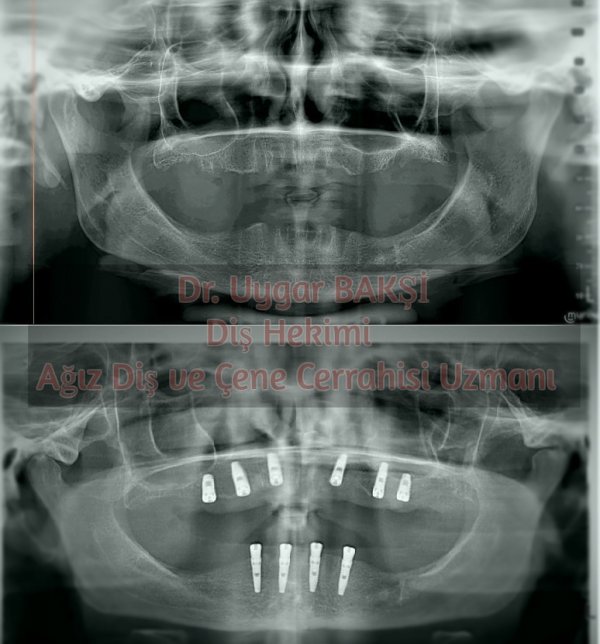

İmplant ameliyatlarının büyük çoğunluğu panoramik rontgen çekilerek gerçekleştirilebilir. Çene kistleri, çene tümörleri, çene ve yüz sinirlerini ilgilendiren uygulamalar ve sinüs ameliyatı gereken vakalar dışında hastadan “tomografi” çekilmesi çoğunlukla, hastaya gereksiz yere radyasyon vermesi açısından yanlış uygulamalardır. Eğer bir diş hekimi, tomografi çekilmesini gerektiren bir vaka ile karşılaştığını düşünüyorsa, o hastayı özellikle uzman hekime yönlendirmelidir; böylesi hasta açısından daha sağlıklıdır.